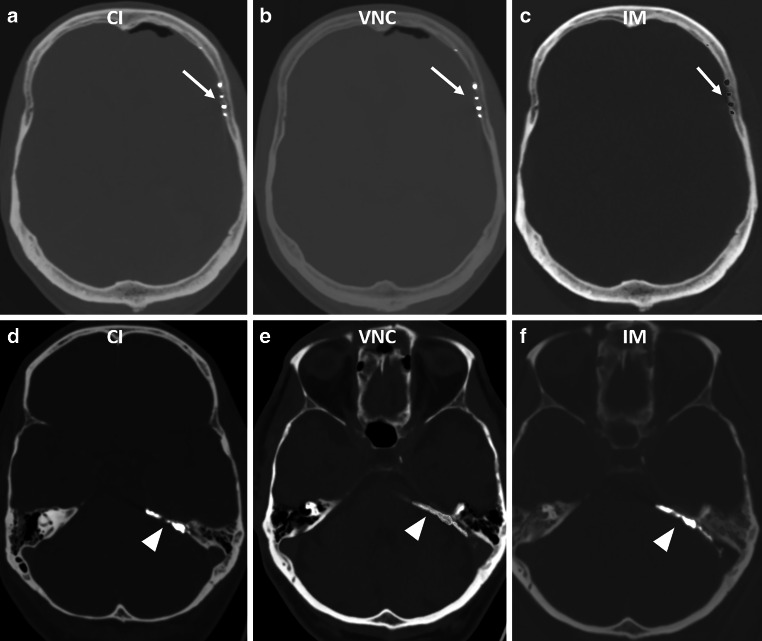

Methods: This retrospective study included 25 patients treated between April 2021 and March 2024, who underwent PCD-CT imaging post-embolization for intracranial arteriovenous malformations (AVM), dural arteriovenous fistulas (dAVF), spinal tumors, or middle meningeal artery (MMA) embolization for chronic subdural hematomas (cSDH). Imaging analysis involved iterative reconstruction, using conventional images (CI), iodine maps (IM), and virtual non-contrast (VNC) series. Two blinded neuroradiologists assessed the suppression quality of the embolic agents on a Likert scale.

Results: Of the 25 patients, 22 underwent intracranial and 3 spinal embolizations. The differentiation between iodine and tantalum-based embolics achieved 92% accuracy for reader 1 and 88% for reader 2, with a Cohen's kappa coefficient of 0.92 indicating high inter-reader agreement. Iodine-based agents were moderately suppressed, whereas tantalum-based agents exhibited superior suppression. Errors arose from mistaking suppressed platinum coils for tantalum-based embolics. Hemorrhage detection accuracy was high, with a Cohen's kappa of 0.92.